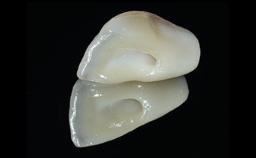

Replacement of an Ankylosed Upper Left Central Incisor: Bone Augmentation and Socket Grafting, Late Placement of an RC Bone Level Implant